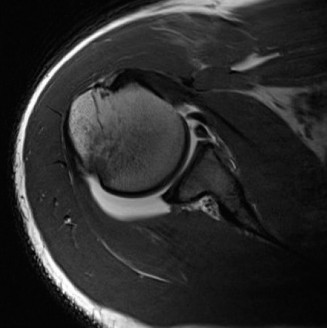

The correct answer is (B). An MRI showing a rotator cuff tear is considered diagnostic of a rotator cuff tear because of its high sensitivity, specificity, and accuracy. It has superb soft tissue imaging abilities (see Fig. 2–5). However, it should be noted that while MRI usually can differentiate between partial- and full-thickness rotator cuff tears, this varies with the power and accuracy of the MRI facility. This is also true with the ability of MRI to differentiate between partial-thickness rotator cuff tears and subacromial bursitis. An arthroscopy is needed for definitive differentiation of these pathologies.

Figure 2–5_Coronal oblique view MRI slice of a left shoulder. (Reproduced with permission from Smithius R and van de Woude HJ. Shoulder MR Anatomy: Normal Anatomy, Variants, and Checklist. _Radiology Assistant. April 2, 2012.)

Shoulder CT scans (Answer A) are not typically used to diagnose rotator cuff tears. X-rays, aka roentgenograms (Answer C), can show signs of rotator cuff pathology but are not diagnostic. Some signs of chronic rotator cuff tears that are sometimes seen on AP view x-rays include calcific tendonitis, calcification of the coracohumeral ligament, proximal migration of the humerus, and cystic changes of the greater tuberosity. An outlet view x-ray can show a type III (hooked) acromion, which is correlated with a higher rate of rotator cuff tears, or an OS acromiale, which would require special consideration for surgical treatment. Shoulder arthrograms (Answer D) are used primarily only when MRI is contraindicated and are considered positive for a rotator cuff tear if dye leaks from the glenohumeral joint into the subacromial space. MR arthrogram (Answer E) has been shown to have equivalent diagnostic ability compared with standard MRI and can be used to diagnose rotator cuff tears. However, it adds an additional step and cost to a standard MRI, and it does not offer any additional diagnostic benefit for rotator cuff pathology. Therefore, standard MRI is preferred to MR arthrogram.